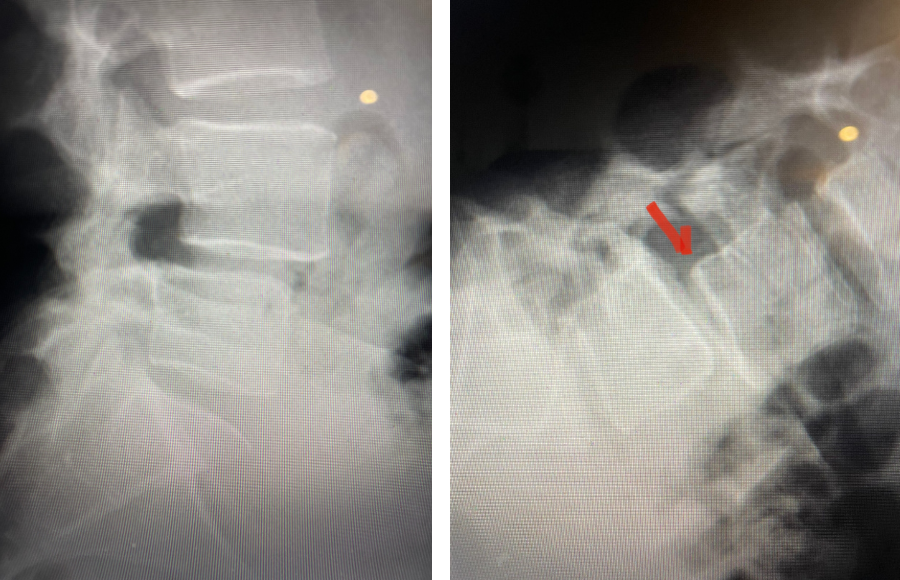

Revision surgery is more involved than primary surgery. In order to start decompressing this large complex, you must develop a plane; you have to find the edge of sometimes a remnant of a lamina or the lamina that can be buried in scar. You must carefully dissect the edge with a sharp upbiting curette and then either using a sharp Leksell to start removing this lamina or use a fine Kerrison to widen the plane and exposure and begin to expose the normal ligamentum above. In this case it was critical to expose and decompress the L3 nerve roots bilaterally. What is quite helpful is finding the inferior edge of the L2 facets. Then one must lift up the inferior L2 process up with a curette and simultaneously insert a Kerrison into joint space and remove the whole facet process. This is a great move because it allows access to the plane between the superior facet and the descending nerve root and a starting point to fully decompress the nerve root. Because of scarring there often is not a clear plane in order to accomplish the decompression. Care is taken to make sure there is a clear separation between edge of bone and dura during the process of inserting a Kerrison edge. The important part of this is feeling your opening and actually using your Kerrison as a dissecting tool once an edge has been established to perform a foraminotomy. We were able to remove the inferior L2 facet process with impunity as we knew we were performing an instrumented fusion to L2. The patient’s had a prior L3-5 instrumented fusion which upon exploration was solidly fused. It was decided to remove her prior hardware as it served its purpose and add a short segment from L2-3 (Fig 5). Patient did well after her surgery with relief of her right leg pain.

Fig 5: intraoperative fluoroscopic images demonstrating L2-3 screw placement.